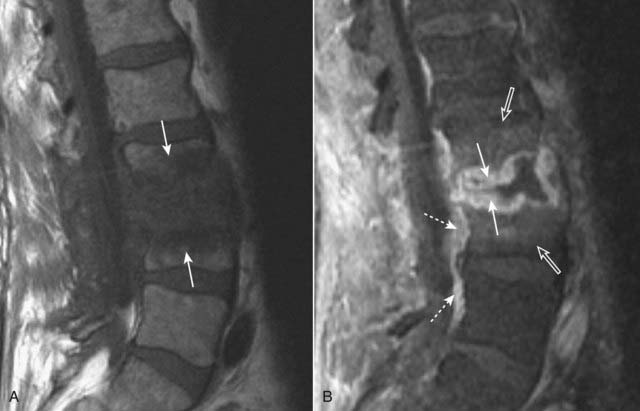

image Recognizing vertebral body osteomyelitis and diskitis on MRI (Fig. 24-17).

Think of diskitis when a process involves two adjacent vertebral bodies and the intervening disk.

On MRI, the involved vertebral body endplates will be T1-dark, often T2-bright, and will enhance on postgadolinium images (these findings alone are not specific and can, in fact, also be seen in the setting of degenerative disk disease).

The involved disk will be diffusely T2-bright and will enhance on postgadolinium images (specific for diskitis).

Epidural abscesses will be T2-bright fluid collections that rim enhance after administration of gadolinium.

Figure 24-17 Osteomyelitis and diskitis, lumbar spine.

A, Sagittal T1-weighted image demonstrates extensive abnormal T1-dark signal indicating destruction of the endplates of the L3 and L4 vertebral bodies and the intervening disk (solid white arrows). B, Sagittal T1-weighted postgadolinium image demonstrates abnormal disk enhancement (solid white arrows) and, more importantly for this diagnosis, enhancement of the adjacent L3 and L4 vertebral bodies (open white arrows). In addition, there is extension to the anterior epidural space (dotted white arrows).